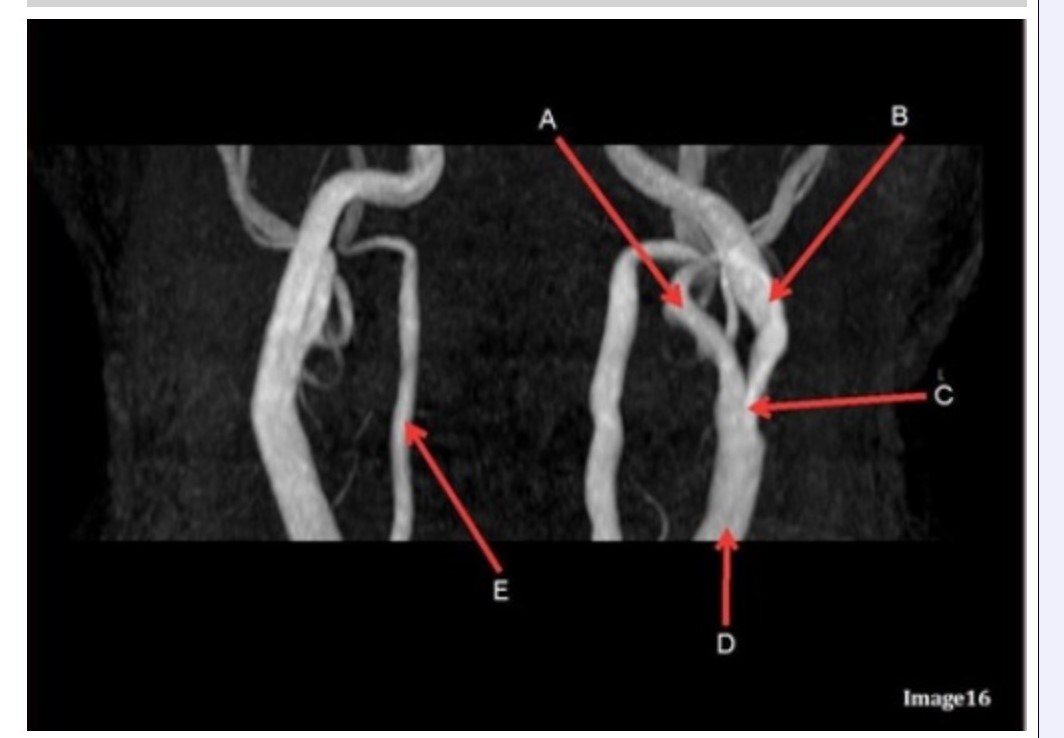

Letter B in Image 16 is pointing to:

A. Internal carotid artery

B. External carotid artery

C. Vertebral artery

D. Common carotid artery

E. Common carotid bifurcation

Letter E in Image 16 is responsible for blood supply to the:

A. Anterior brain

B. Posterior brain

C. Face

D. Upper extremities

Letter D in Image 16 is pointing to:

A. Internal carotid artery

B. External carotid artery

C. Vertebral artery

D. Common carotid artery

E. Common carotid bifurcation

Image 16 is an example of what type of MR image?

A. MR spectroscopy

B. MRA Circle of Willis

C. MRV intracranial circulation

D. MRA extracranial circulation

E. MRA intracranial circulation

Letter B in Image 16 is responsible for blood supply to the:

A. Anterior brain

B. Posterior brain

C. Face

D. Upper extremities

Letter E in Image 16 is pointing to:

A. Internal carotid artery

B. External carotid artery

C. Vertebral artery

D. Common carotid artery

Letter C in Image 16 is pointing to:

A. Internal carotid artery

B. External carotid artery

C. Vertebral artery

D. Common carotid artery

E. Common carotid bifurcation

Letter A in Image 16 is pointing to:

A. Internal carotid artery

B. External carotid artery

C. Vertebral artery

D. Common carotid artery

E. Common carotid bifurcation

Letter A in Image 16 is responsible for blood supply to the:

A. Anterior brain

B. Posterior brain

C. Face

D. Upper extremities